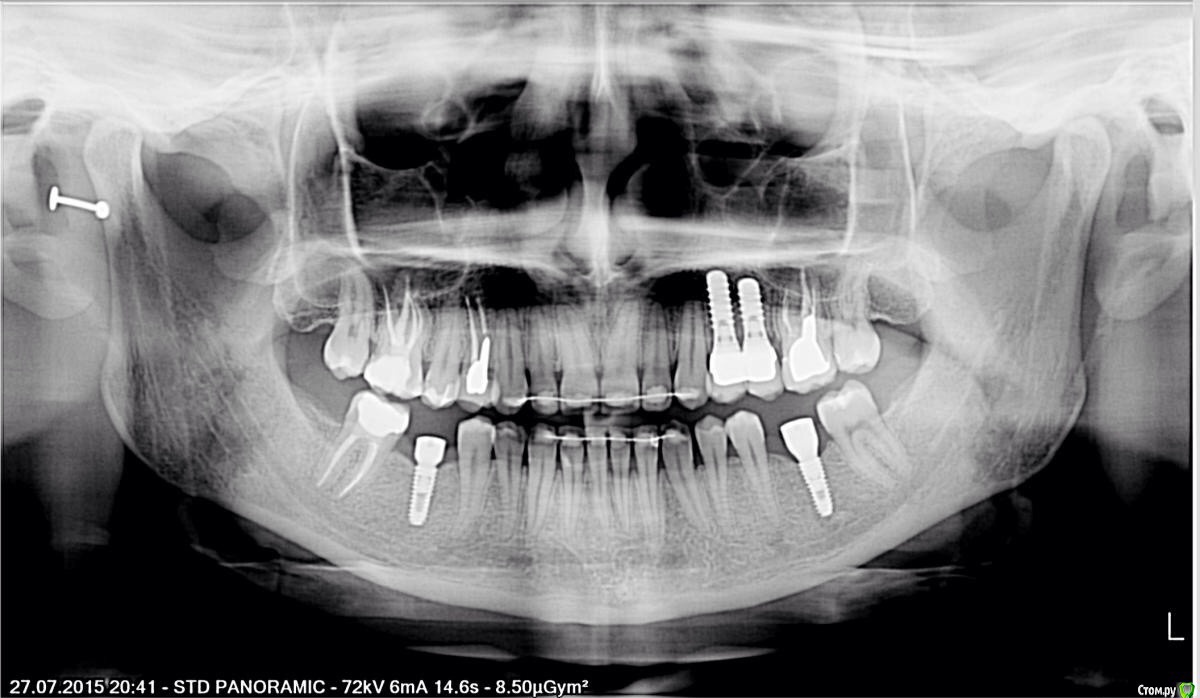

Тая.А Опубликовано 10 августа, 2015 Поделиться Опубликовано 10 августа, 2015 (изменено) Здравствуйте, еще раз. С проблемой одних и тех же зубов пишу сюда не в первый раз. Скажу сразу, что собираюсь переделывать работу уже в 3 раз, хотя уже надоело разбираться с этими зубами и тратить большие деньги!Что волнует:1. 3 зуба с левой верхней стороны (2 на имплантатах рядом, один с вкладкой под коронкой, то есть 4,5,6)2. Изначально плохо видимо пролечили 4 и 5, там образовалась киста, подождала, удалила, поставила имплантаты, десну разворотило, 6-му зубу видимо тоже досталось, десна не плотно прилегает.3. Эстетически результат протезирования на имплантатах не устроил совсем, хирургом в принципе довольна, супер сосочков между имплантатами уже не жду, ожидаю пластикой немного опустить десну или удалить один из имплантатов и сделать сосочки,4. Теперь образовался еще важный вопрос, наравне с эстетикой.В связи с тем, что с десной не очень понятная ситуация, теперь я чувствую еще и неприятный слабый запах с той стороны (4,5,6 не пойму откуда).это правда мешает жить и нервирует, поэтому прежде, чем определиться с дальнейшим планом лечения, спрошу:-сделана ли коронка на 6 зубе с уступом и ПО всем правилам ( если я ногтем могу нащупать переход от шейки зуба к коронке)может ли из-за этого быть запах?-имплантаты на индивидуальных абатментах, все безметалловое ( циркон+eMax), или запах отсюда?-и вот что с этим вообще делать? P.S. Последнее вот никак не удалось перевернуть. Изменено 10 августа, 2015 пользователем Тая.А Ссылка на комментарий